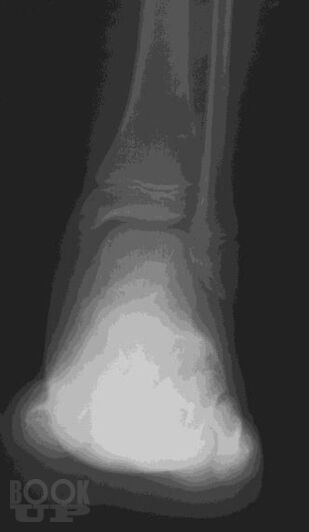

В учебном пособии представлены общие положения о развитии и анатомии опорно-двигательного аппарата, методы лучевой диагностики и показания для их использования при исследовании костей и суставов, изложены основы посиндромного подхода к диагностике заболеваний костно-суставной системы, основы диагностики травматических повреждений.